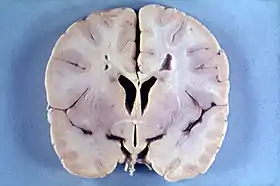

![]() مخ طفل 4 أعوام مصاب بمرض أليكساندر، تظهر الصورة ضخامة الدماغ مع تصبغ بني اللون حول بطينات الدماغ مخ طفل 4 أعوام مصاب بمرض أليكساندر، تظهر الصورة ضخامة الدماغ مع تصبغ بني اللون حول بطينات الدماغ | |